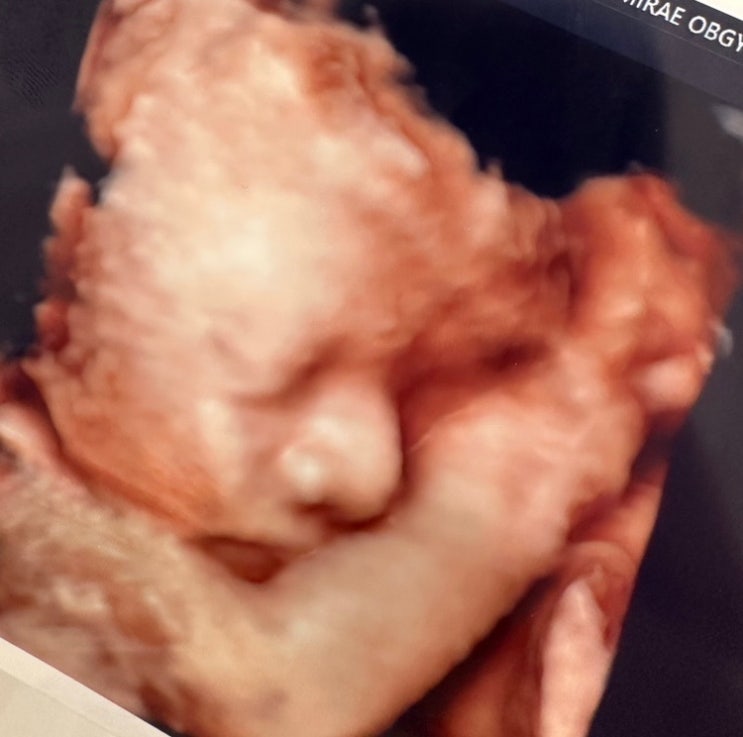

33주 5일 | 9개월 임산부 | 경산맘 | 경부길이 짧음 | 폐성숙주사 | 고위험산모

또 일주일이 지났습니다. 일주일 동안 열심히 카페에도 보고 유튜브도 보고 그러다 보니 지금 주수에는 수...